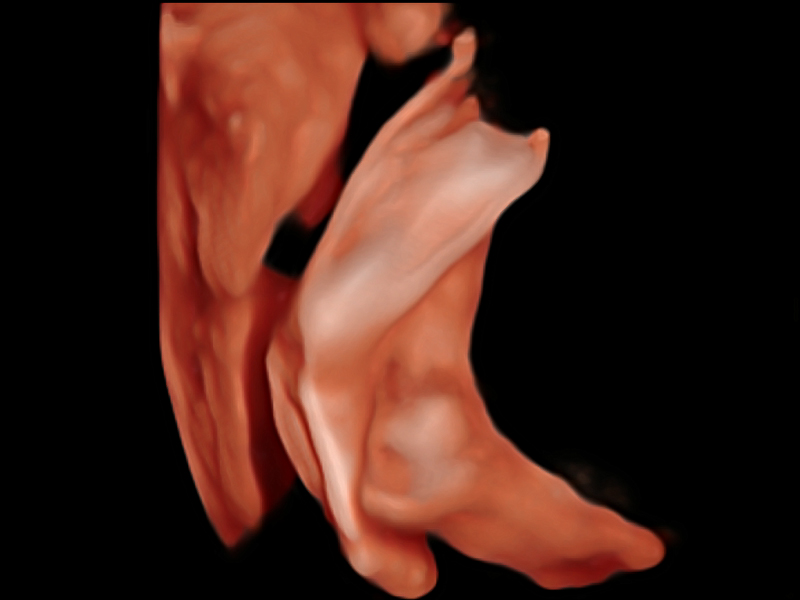

μ-Scan+新一代微米成像技术

新一代微米成像技术大大提高了器官和病变的可见性。高清对比度分辨率将抑制斑点噪声,同时保持真实的组织结构。